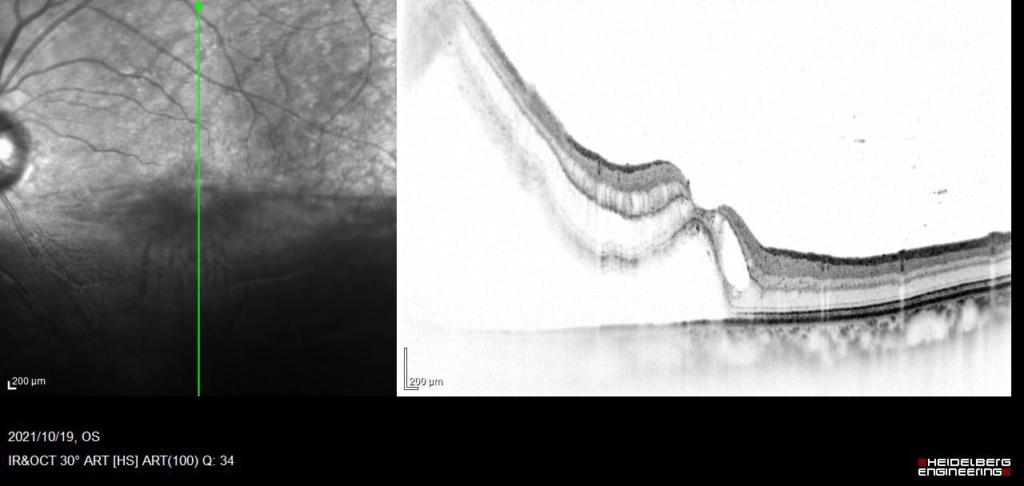

中心窩を含んで網膜剥離があり、外網状層の浮腫と嚢胞様変化がみられる。